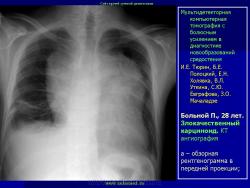

Средостение.  "Опухолевый рост".